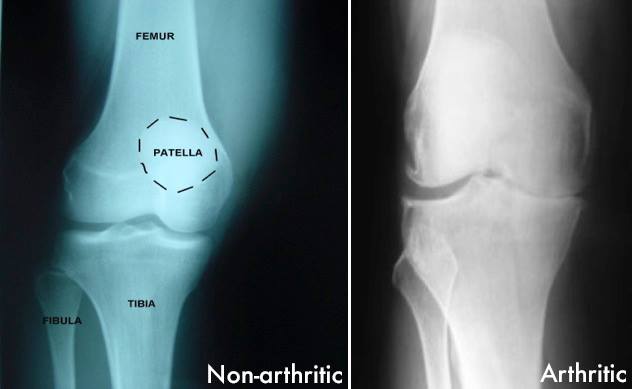

Just because it looks good, doesn’t mean that it is.

We have all had patients with seemingly negative knee x rays and pain, only to develop arthritic changes at a later date. Find and treat the cause!